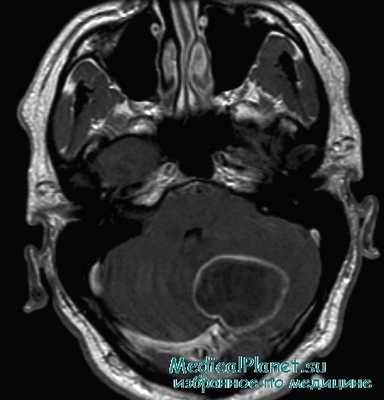

МРТ при абсцессе мозжечка

МРТ головного мозга — более точный метод диагностирования. При проведении МРТ на первых стадиях формирования абсцесса мозга (1-9 сутки) энцефалитический очаг выглядит: на Т1-взвешенных изображениях — гипоинтенсивным, на Т2-взвешенных изображениях — гиперинтенсивным. МРТ на поздней (капсулированной) стадии абсцесса головного мозга: на Т1-взвешенных изображениях абсцесс выглядит, как зона пониженного сигнала в центре и на периферии (в зоне отека), а по контуру капсулы сигнал гиперинтенсивный. На Т2-взвешенных изображениях центр абсцесса изо- или гипоинтенсивный, в периферической зоне (зоне отека) гиперинтенсивный. Контур капсулы четко очерчен.

д) Клиническая картина абсцесса мозжечка:

• Нарушение координированных движений глазных яблок и функции постуральной системы.

• Нистагм: грубый спонтанный нистагм, направленный в сторону поражения, вестибулярный нистагм с нерегулярным позиционным нистагмом, нистагм направленного взора, связанный со вторичным повреждением моста; нистагм при парезе взора, направленный в сторону поражения.

• Атаксия, интенционный тремор, дисметрия, адиадохокинез, гипотензия; симптомы, обусловленные распространением воспалительного процесса на соседние структуры, например паралич ЧН III, V—VII, IX и X.